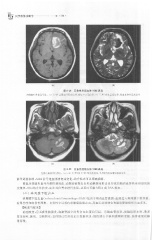

Page 320 - 医学影像诊断学